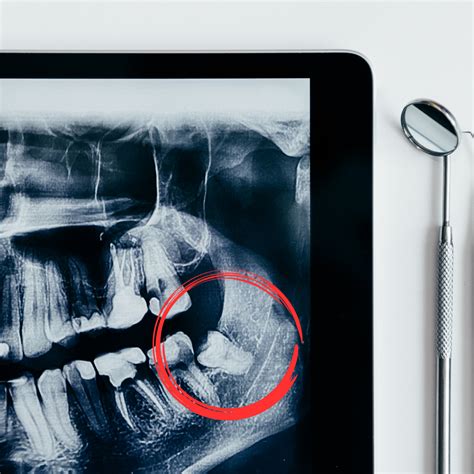

Si tienes molestias en la parte anterior de la boca, lo primero que tienes que hacer es acudir al dentista. O simplemente, entre los 17 y 21 años realizar una radiografía para detectar su presencia y que tu dentista pueda realizar una valoración. Actualmente los dentistas podemos aconsejar o no su extracción, dependiendo de cada caso que hay que analizar con una radiografía de la boca.